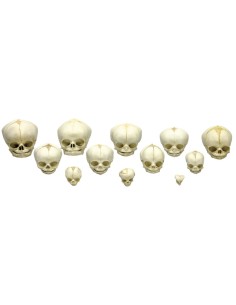

Dal cranio in 22 parti con incastri magnetici ai modelli di colonna vertebrale, da quelli di articolazioni a quelli di cuore, ogni pezzo della nostra collezione è progettato per un’immersione totale nello studio dell’anatomia umana. I nostri modelli, realizzati tramite scansioni di ossa vere, garantiscono un’esperienza tattile autentica e una fedeltà di peso quasi identica agli originali.

Essenziali per studenti e professionisti, i nostri modelli anatomici sono strumenti didattici che permettono di osservare le strutture anatomiche con precisione, eliminando la necessità di dissezioni o studi invasivi. Sono inoltre utili per spiegare ai pazienti le patologie, rendendo la comunicazione più efficace e risparmiando tempo prezioso.